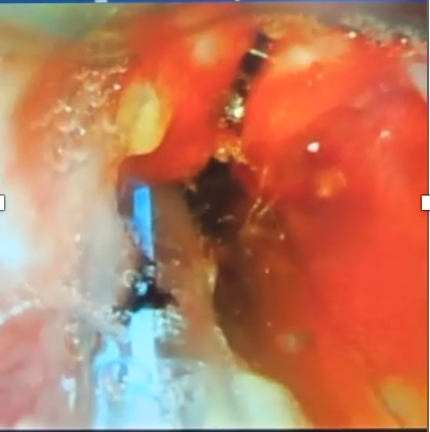

Ventilator air leak prompted re-intubation with a size 3.5 tube. Videolaryngoscopy revealed a slit-like laryngeal deformity (Figure 1.). Bedside echocardiography reaffirmed DORV with pulmonary stenosis. Initial chest radiography (Figure 2.) showed a left lower lobe opacity and a feeding tube in the distal esophagus. The initial impression included neonatal pneumonia with polymalformative features: possible laryngeal cleft, double outlet right ventricle (DORV), esophageal atresia (EA), and tracheoesophageal fistula (TEF). Upon admission, empiric IV antibiotics were started. Referrals to Pediatric Cardiology for evaluation of DORV and to Pediatric Surgery for assessment of suspected EA/TEF were made. A Pediatric Pulmonology consult was eventually obtained for airway assessment due to consideration of laryngotreacheoesophageal cleft.

Video laryngoscopy showing slit-like deformity

Figure 1. Video laryngoscopy during intubation showing a slit-like deformity bisecting the laryngeal area.